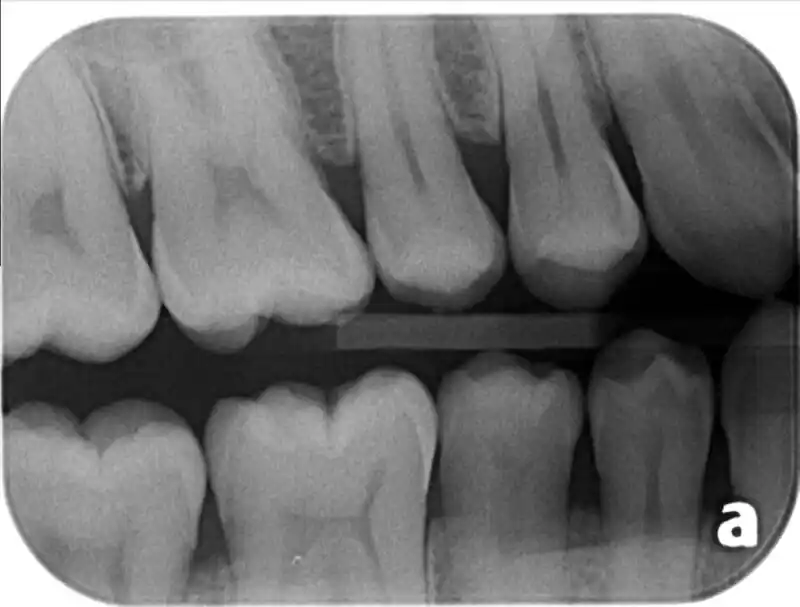

En PlayDent Quinta Normal contamos con un moderno servicio de radiografías dentales, diseñado para ofrecer un diagnóstico preciso, seguro y rápido a nuestros pacientes. Si estás buscando radiografías dentales en Quinta Normal, en nuestra clínica encontrarás tecnología de última generación y un equipo profesional capacitado para brindarte una atención de calidad. ¿Qué son las radiografías […]